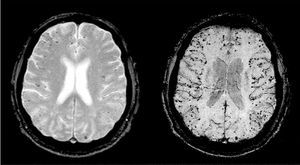

Para el diagnóstico del ictus hemorrágico es esencial la práctica de la neuroimagen. Se sospecha ante la clínica de focalidad neurológica aguda, y la TC-C o la RM detectarán el sangrado. Secuencias específicas de RM de gradiente eco que detectan el efecto paramagnético de la desoxihemoglobina y la metahemoglobina permiten detectar sangrados crónicos parenquimatosos (microbleeds) (fig. 7).

Fig. 7. Microsangrados. Imagen por resonancia magnética con secuencias de eco-gradiente que muestra microsangrados (microbleeds) corticales compatibles con angiopatía amiloide cerebral.